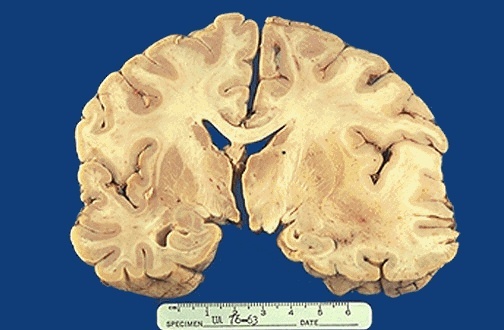

Cerebral edema shift of midline to the left

Cerebral edema wide gyri narrow sulci